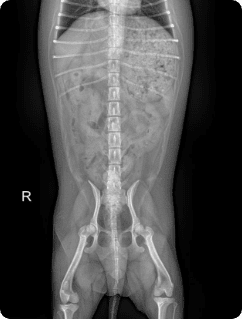

일산시티동물의료센터 방사선(X-ray) 검사는 탁월한 영상품질로 세밀하고 선명한 영상을 얻을 수 있습니다.

간, 비장, 소화기, 콩팥, 방광, 부신의 종양, 간문맥전신단락, 복강 내 실질 장기 평가, 요로결석에 의한 폐색 평가

골절, 골종양 등